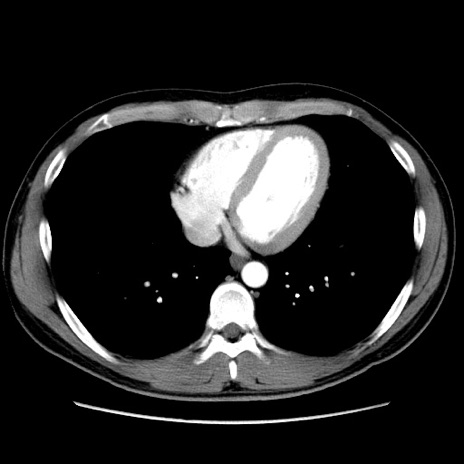

冠状断像

【症例】20歳代 男性

【主訴】心窩部痛

【現病歴】今朝より上腹部痛あり。一旦軽快していたが再度出現したため救急要請。昨日夕に白身の魚を含む刺身を食べた。

【身体所見】BP 136/89mmHg、HR 74/min、BT 37.0℃、腹部:膨満、軟、心窩部に圧痛あり。反跳痛なし、筋性防御なし、腸雑音やや亢進あり。

【データ】WBC 17700、CRP 0.48